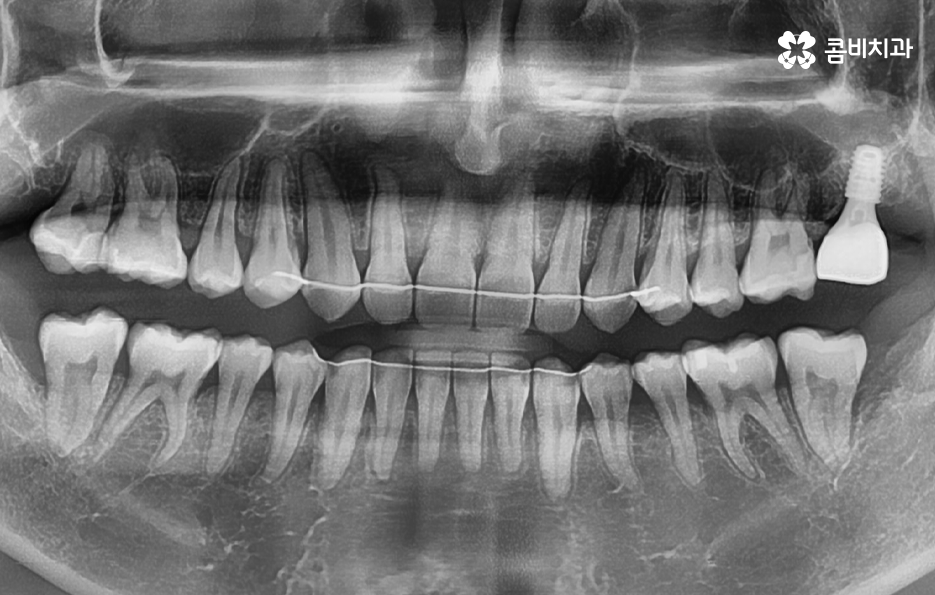

치아 발치 후에는 보통 약 2,3개월 정도 잇몸과 뼈가 차오르길 기다리며 그 이후에 잇몸 상태가 임플란트를 식립하기에 충분한 상태라면 임플란트를 잇몸 뼈에 식립하고 골유착과정을 약 3개월 정도 거친 후에 지대주를 세우고 보철물을 연결하여 치료를 마무리하고 있어요. 하지만 잇몸뼈 상태가 좋거나, 뼈이식과 동시에 진행하는 경우 발치 후 바로 식립을 진행하는 경우도 있어, 정확한 치료 계획은 의사와 상의를 해보시는 게 좋아요.

임플란트 치료가 끝나면 겉으로 보기에는 자연치아와 거의 유사한 심미성과 적응기간을 거치고 나면 저작력에 있어서 자연치아와 거의 유사한 정도의 저작기능을 수행하고 있는데요

어금니 발치후 임플란트 치료과정은 단계적으로 진행되고 일반적으로 임플란트 구조는 분리형이기 때문에 시술 후 관리 방법에 따라서 보철물의 이상 발생 시에는 사후관리를 통해 해결할 수 있지만 잇몸 뼈에 식립된 인공치근이 염증 등으로 인해 문제가 생기면 심각한 수명 문제로 이어질 수 있기 때문에 사후관리의 중요성이 무척이나 크며 치료만 잘 받는 것이 아니라 오랫동안 꾸준히 사후관리를 믿고 찾을 수 있는 치과를 잘 선택하실 필요가 있어요